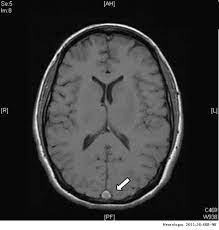

Nueva guía para el diagnóstico y tratamiento de la trombosis venosa cerebral

En esta patología, mucho menos frecuente que la enfermedad cerebrovascular de causa arterial, las evidencias son también menos concluyentes. La European Stroke Organization actualiza sus recomendaciones y señala las áreas de incerteza. European Journal of Neurology, agosto de 2017